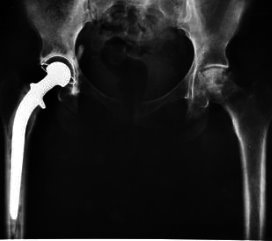

Rapid Recovery ook geschikt voor 85-plussers

Verpleegkundig specialist orthopedie Sabine Siepelinga vroeg zich af of het Rapid Recovery programma voor totale heuppatiënten ook goed werkt bij 85+ers.